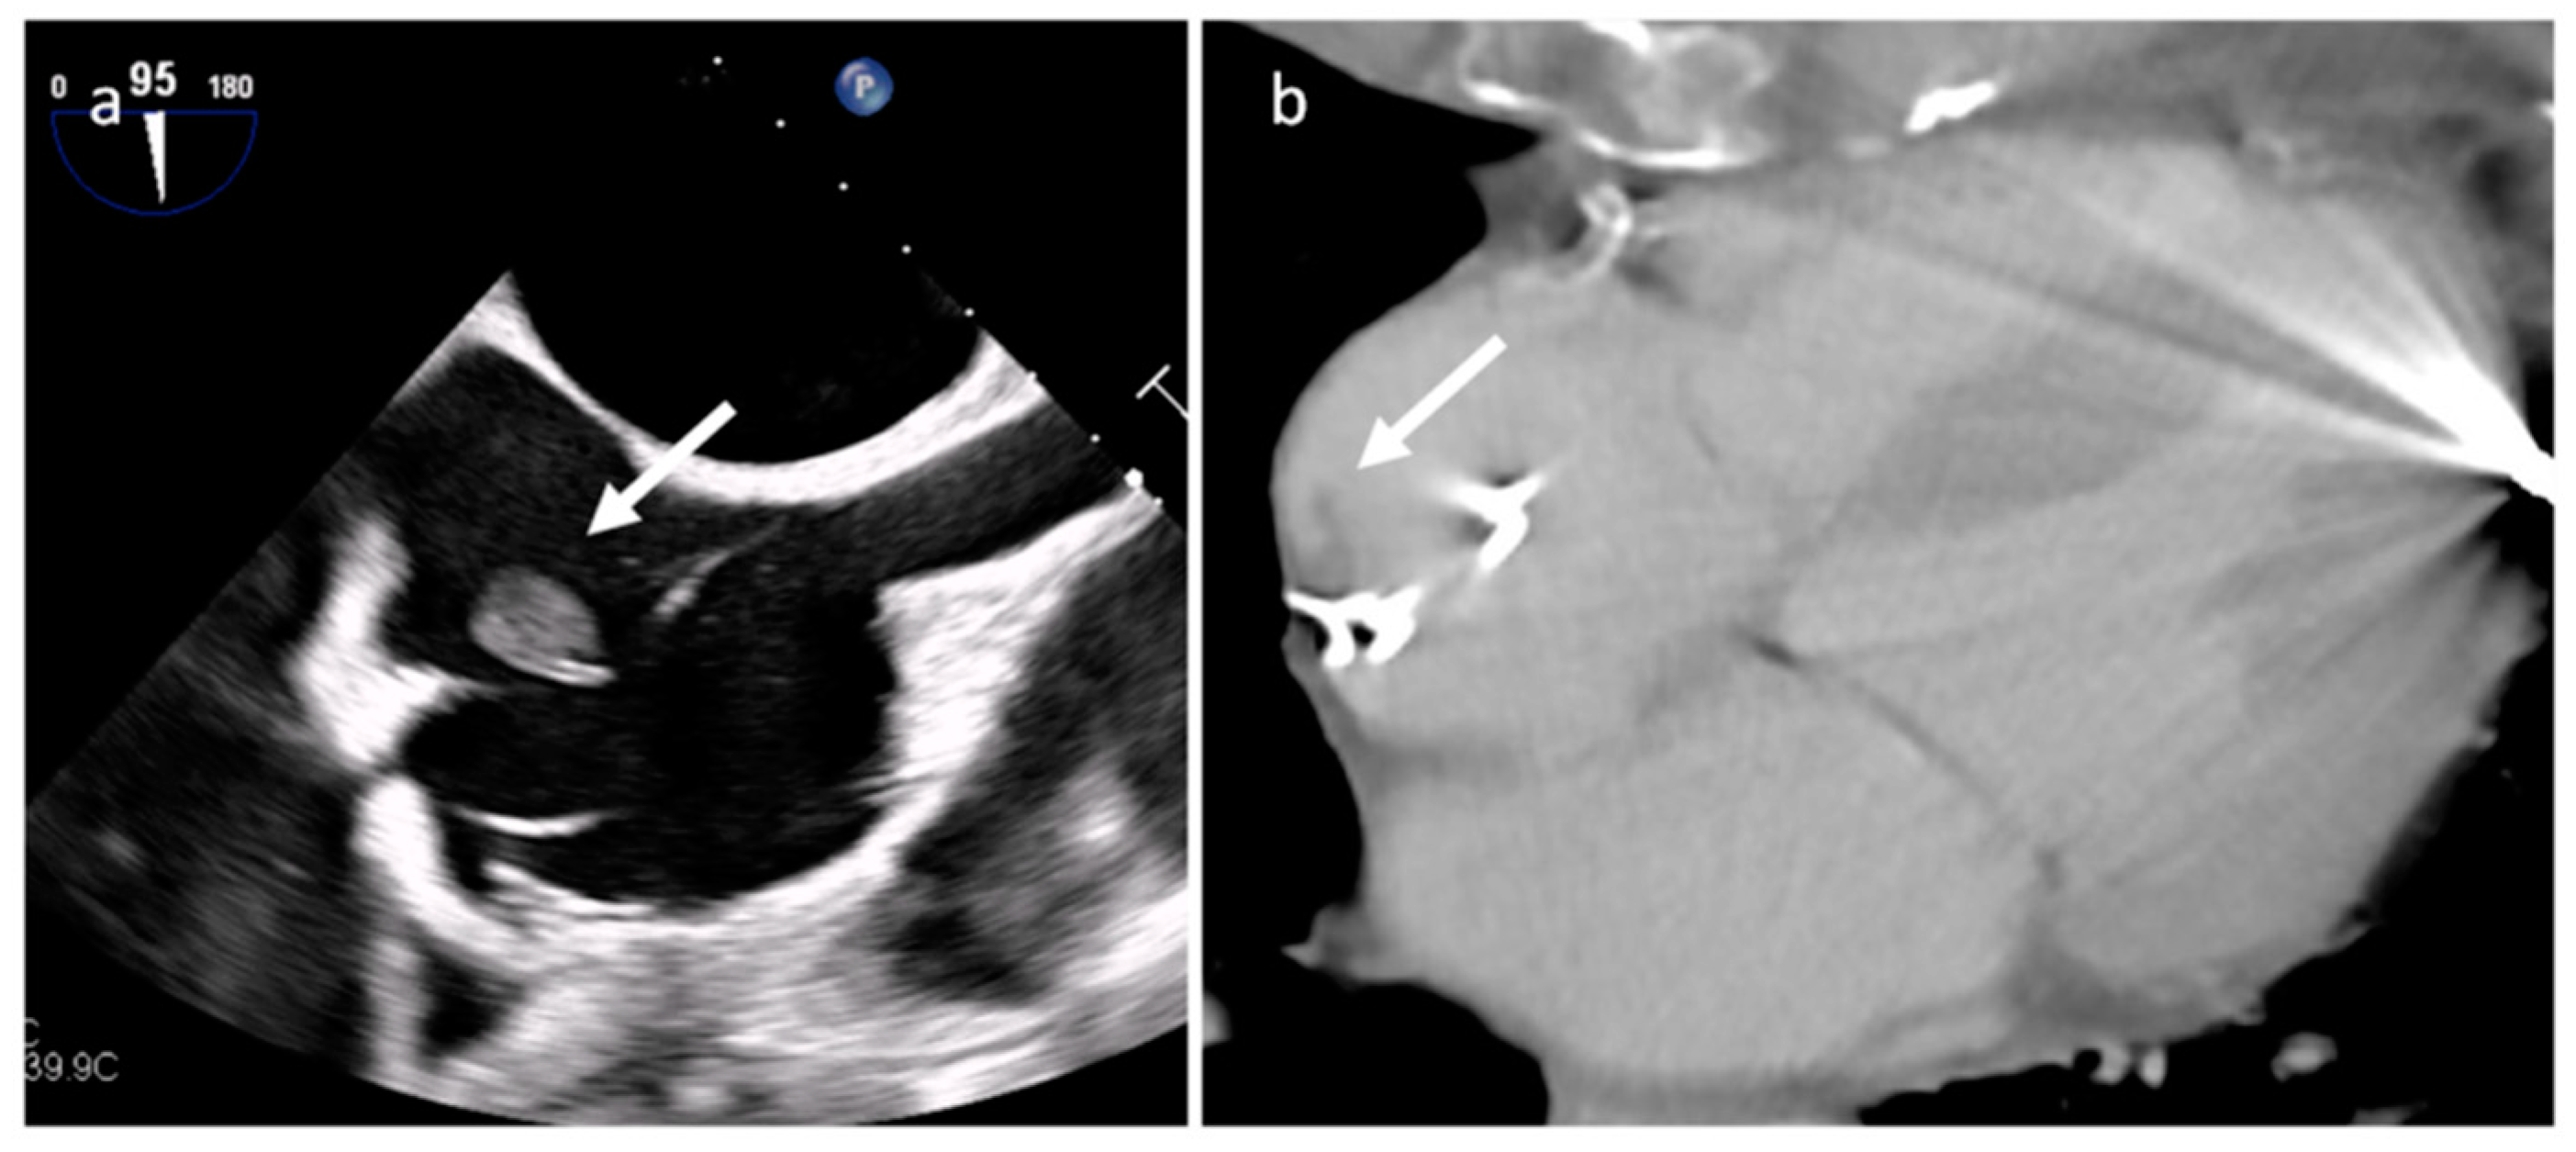

3.2. Vegetations

| Vegetations | Adulthood | Valves | Valve dysfunction, emboli, heart failure | Highly mobile, non-enhancing | Highly mobile, oscillating, protruding, valve dysfunction | Low attenuation, may recognize, perivalvular extension, fistulas, abscess | Highly mobile |